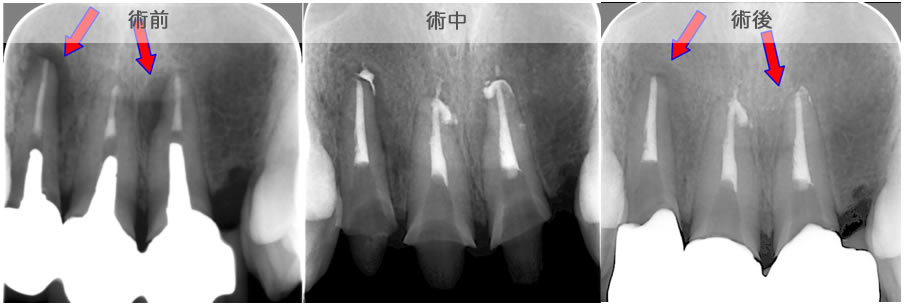

| 治療説明 | 上顎前歯部の根尖部からの排膿があります。歯冠補綴物とメタルコアを除去し、根管治療を行いました。根尖部から根充剤が漏れてはみ出していましたが、X線透過像は消失しました。 |

|---|---|

| 治療場所 | 上顎前歯部 |

| 原因 | 根尖病巣 |

| 治療期間 | 6〜24ヶ月 |

| 治療費用 | 150,000〜300,000円 |

| 治療に伴うリスク | 根管内からの治療で根尖病巣が治らない場合は、外科的に根尖病巣を除去する必要があります。 再根管治療を繰り返す場合、歯根の厚みが薄くなり、歯根破折のリスクが高まります。 |